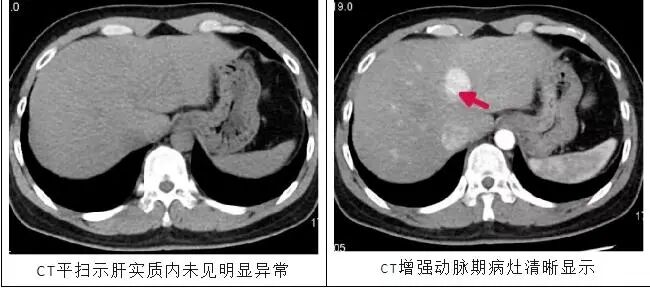

1、提高对病灶的检出率 ,减低漏诊率:普通CT平扫未发现或者显示不佳的病灶,引入对比剂后,不同病变及组织对对比剂的吸收和分布不同,使得病变组织和病变组织之间有了明显的区分。

图片